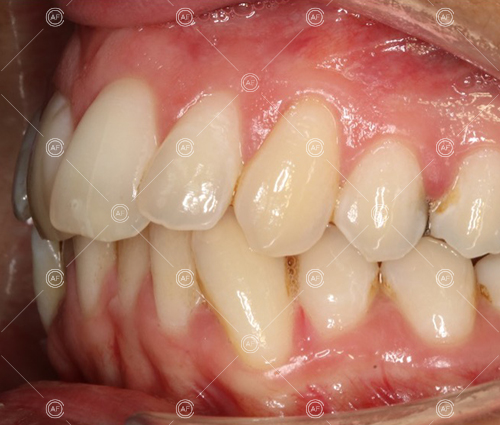

Residual space from the extractions were closed using upper and lower nickel titanium closing coils. Class 2 elastics were used to facilitate space closure in order to gain class 1 buccal segments.

MH debonded in December 2020, with overall treatment time of around 14 months.

She was provided with upper and lower vacuum form retainers, and asked to wear these every night for the first year, and alternate nights for the second year onwards, indefinitely for as long as she wanted her teeth to remain straight. High quality finish was maintained at one year post-debond.